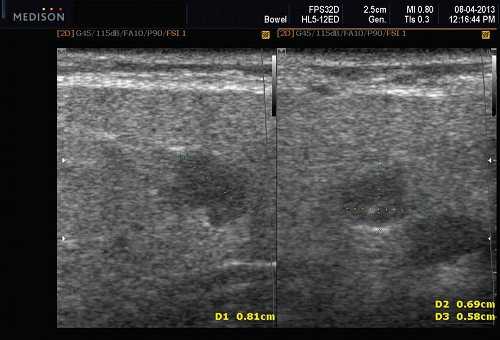

Плеоморфная (полиморфная) аденома (смешанная опухоль СЖ) - аденома СЖ, построенная из двух типов клеток: эпителия протоков и миоэпителиоцитов. Макроморфологическая картина. Опухоль обычно представляет собой эластичный или плотный узел дольчатой серовато-белой ткани, как правило, инкапсулированный частично. Типичной для плеоморфной аденомы является так называемая хондроидная строма, напоминающая гиалиновый хрящ. Варианты эхографического изображения плеоморфных аденом представлены на рисунке 8.